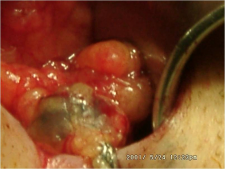

- ניתן להזריק חומר צבע הנספג במערכת הלימפתית וצובע את הבלוטות או חומר רדיואקטיבי המסמן את הבלוטות. בכל מקרה, החומר צריך להיות סגולי, כלומר להיספג רק למערכת הלימפתית. חומר הצבע מוזרק כעשר דקות לפני הניתוח סביב השאת ובניתוח ניתן לראות היטב את כלי הלימפה הצבועים ואת הבלוטות הצבועות (תמונה 51.12).

החומר הרדיואקטיבי מוזרק כארבע שעות עד 24 שעות לפני ניתוח. לאחר הזרקתו בעזרת מיפוי אפשר להדגים את מקום הבלוטה ולסמן את מיקומה על העור. ניתן להדגים גם בלוטות הקולטות חומר בשרשרת האינטרנל ממרי. בחדר ניתוח ניתן לאתר את הבלוטה בעזרת מונה גייגר על העור ובשדה הניתוח (תמונה 52.12).

חומרי צבע כאלה הם: Patent blue, Lymphozorin ו- Isosulfan blue. החומר הרדיואקטיבי הוא ננוקולואיד (ריניום) מסומן בטכנציום 99. יתרון הצבע הוא: מחירו הנמוך, זמינותו והיכולת להזריקו כ-10 דקות לפני הניתוח ולקבל צביעה של הבלוטות. חסרונותיו הם: בכ-14% מהמוזרקות לא ניתן לזהות את בלוטת זקיף, הצבע המוזרק מפריע בזמן ניתוח השד מכיוון שצובע את שדה הניתוח ותגובה אלרגית לחומר המדווחת ב-1 ל-1000 הזרקות הגורמת לשוק אנפילקטי חמור. יתרונות החומר הרדיואקטיבי הם: אמינותו הגבוהה יחסית לצבע בזיהוי בלוטות - 93%, היכולת לזהות בלוטות בשרשרת באינטרנל ממרי ושדה ניתוח נקי יחסית. חסרונותיו הם: מחירו הגבוה, הצורך במכשור יעודי יקר ומשך ההמתנה מההזרקה ועד מועד הסימון של הבלוטה.